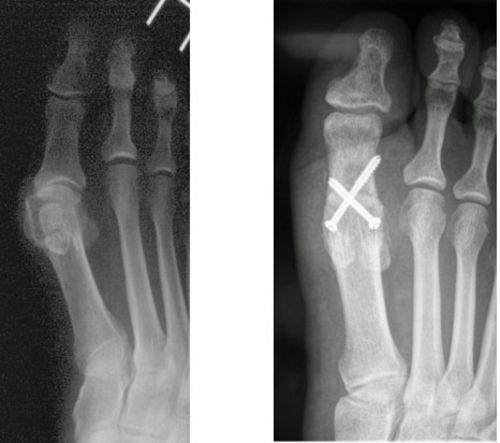

Abb.9: a Fixierte Krallenzehenfehlstellung mit Clavus (Hühnerauge).

b Der störende Knochen wird entfernt (Resektionsarthroplastik nach Hohmann)